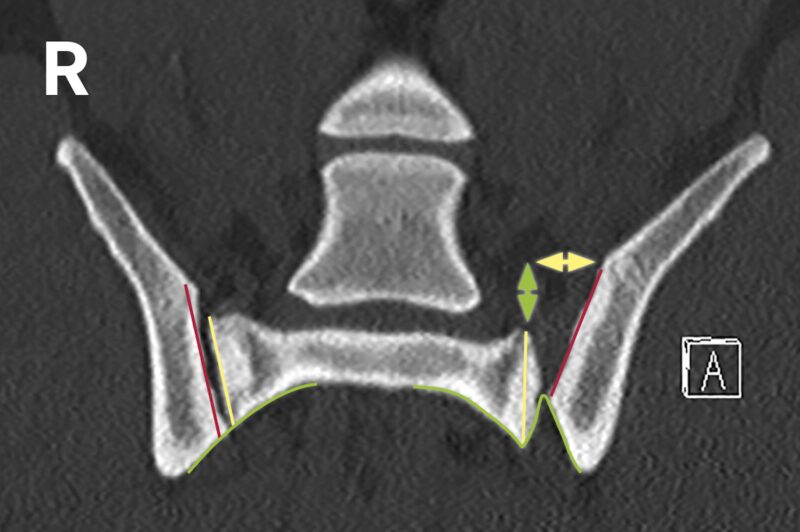

Der Befund ergibt eine iliosakrale Luxation bzw. Diastase. Die Stufe in den Konturen zeigt die Luxation des Darmbeins nach kranial (grün). Die Verbreiterung des Gelenkspalts zeigt die Dislokation des Darmbeins nach lateral (gelb).